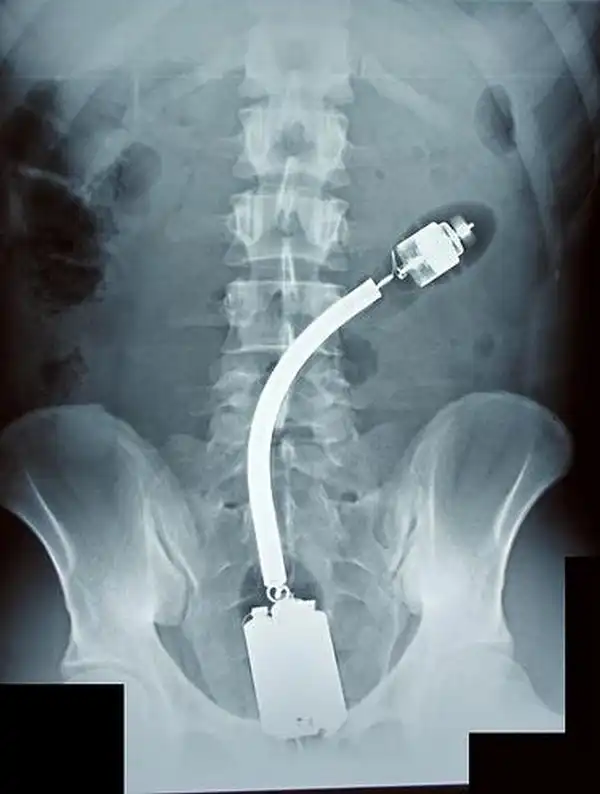

Лампочки, бутылки, флакончики и т.д.

Что они делали и зачем, остается загадкой :hmm:

по-моему на многих явный фотошоп, например на последней, если кто знает как работает рентген, то он поймет что такой снимок физически невозможен.

На фотке с бутылкой кока-колы у пациента еще и искусственный сустав бедра.

Вообще то по строению таза видно м или ж.

Пояснять все отличия не буду, долго (читайте анатомия костей таза). Но именно по тазу определяется половая принадлежность скелета человека при экспертизах.

Не размер, а строение и форма костей а также лобкового симфиза.

Ну да, или просто руками смотря что и как застряло. Просто бывает что сама вытащить не может, а у доктора получается.